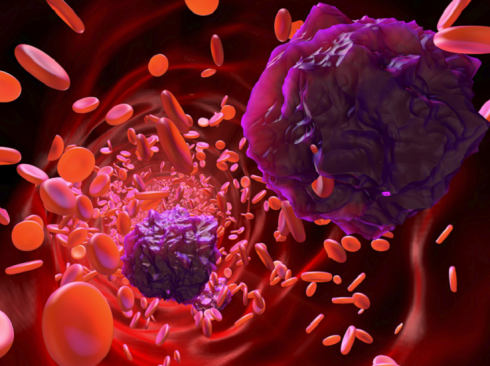

دواء جديد يحمي القلب ويعزز علاج السرطان في آن واحد